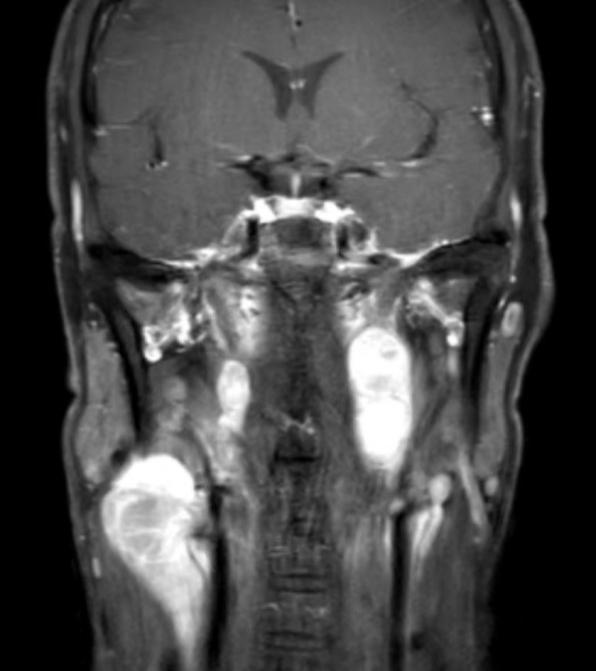

患者影像资料

患者赵某,男性,46岁,1年前开始发现右颈包块,指甲大小,未诊治。1年来包块逐渐增大增多,现大者约6*7cm,3个月前开始出现鼻塞,伴清水样鼻涕,于右鼻腔肿物取病理出血较多,病理回报:肿瘤性病变。局麻下行淋巴结活检,转移性恶性肿瘤,符合转移性高级别嗅神经母细胞瘤,磁共振见鼻腔鼻窦肿瘤似累及右侧额叶。甲状腺头颈外科二病区樊新龙医生接诊此患者,患者及家属手术愿望迫切。

患者入院后,甲状腺头颈外科二病区立即组织多学科会诊,专家组充分评估病情:患者鼻腔鼻窦恶性肿瘤,侵及前颅窝底硬膜内外,双颈淋巴结多发转移,上至咽旁,需请神经外科联合开颅手术,手术复杂、难度大,风险高。